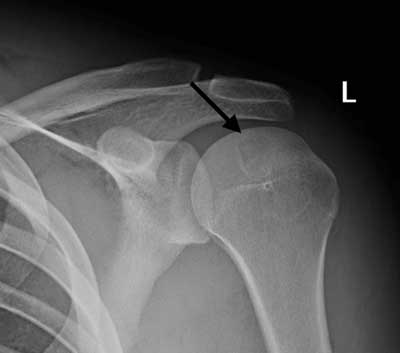

Figure 2

Radiograph of the left shoulder, AP view: a rounded lytic lesion is seen in the epiphysis of the humeral head, with sharp borders and a thin sclerotic rim (arrow).